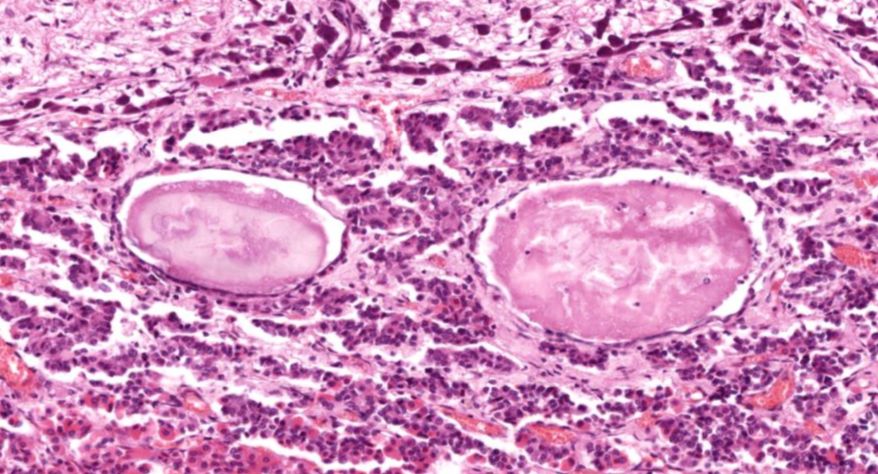

弥漫性非毒性甲状腺肿:甲状腺滤泡明显扩张,内含大量胶质,滤泡上皮细胞受压呈扁平状。部分上皮增生,可见小滤泡和小假乳头形成。

1.全景图

2.纤维组织包膜

3.滤泡上皮增生

4.滤泡扩张